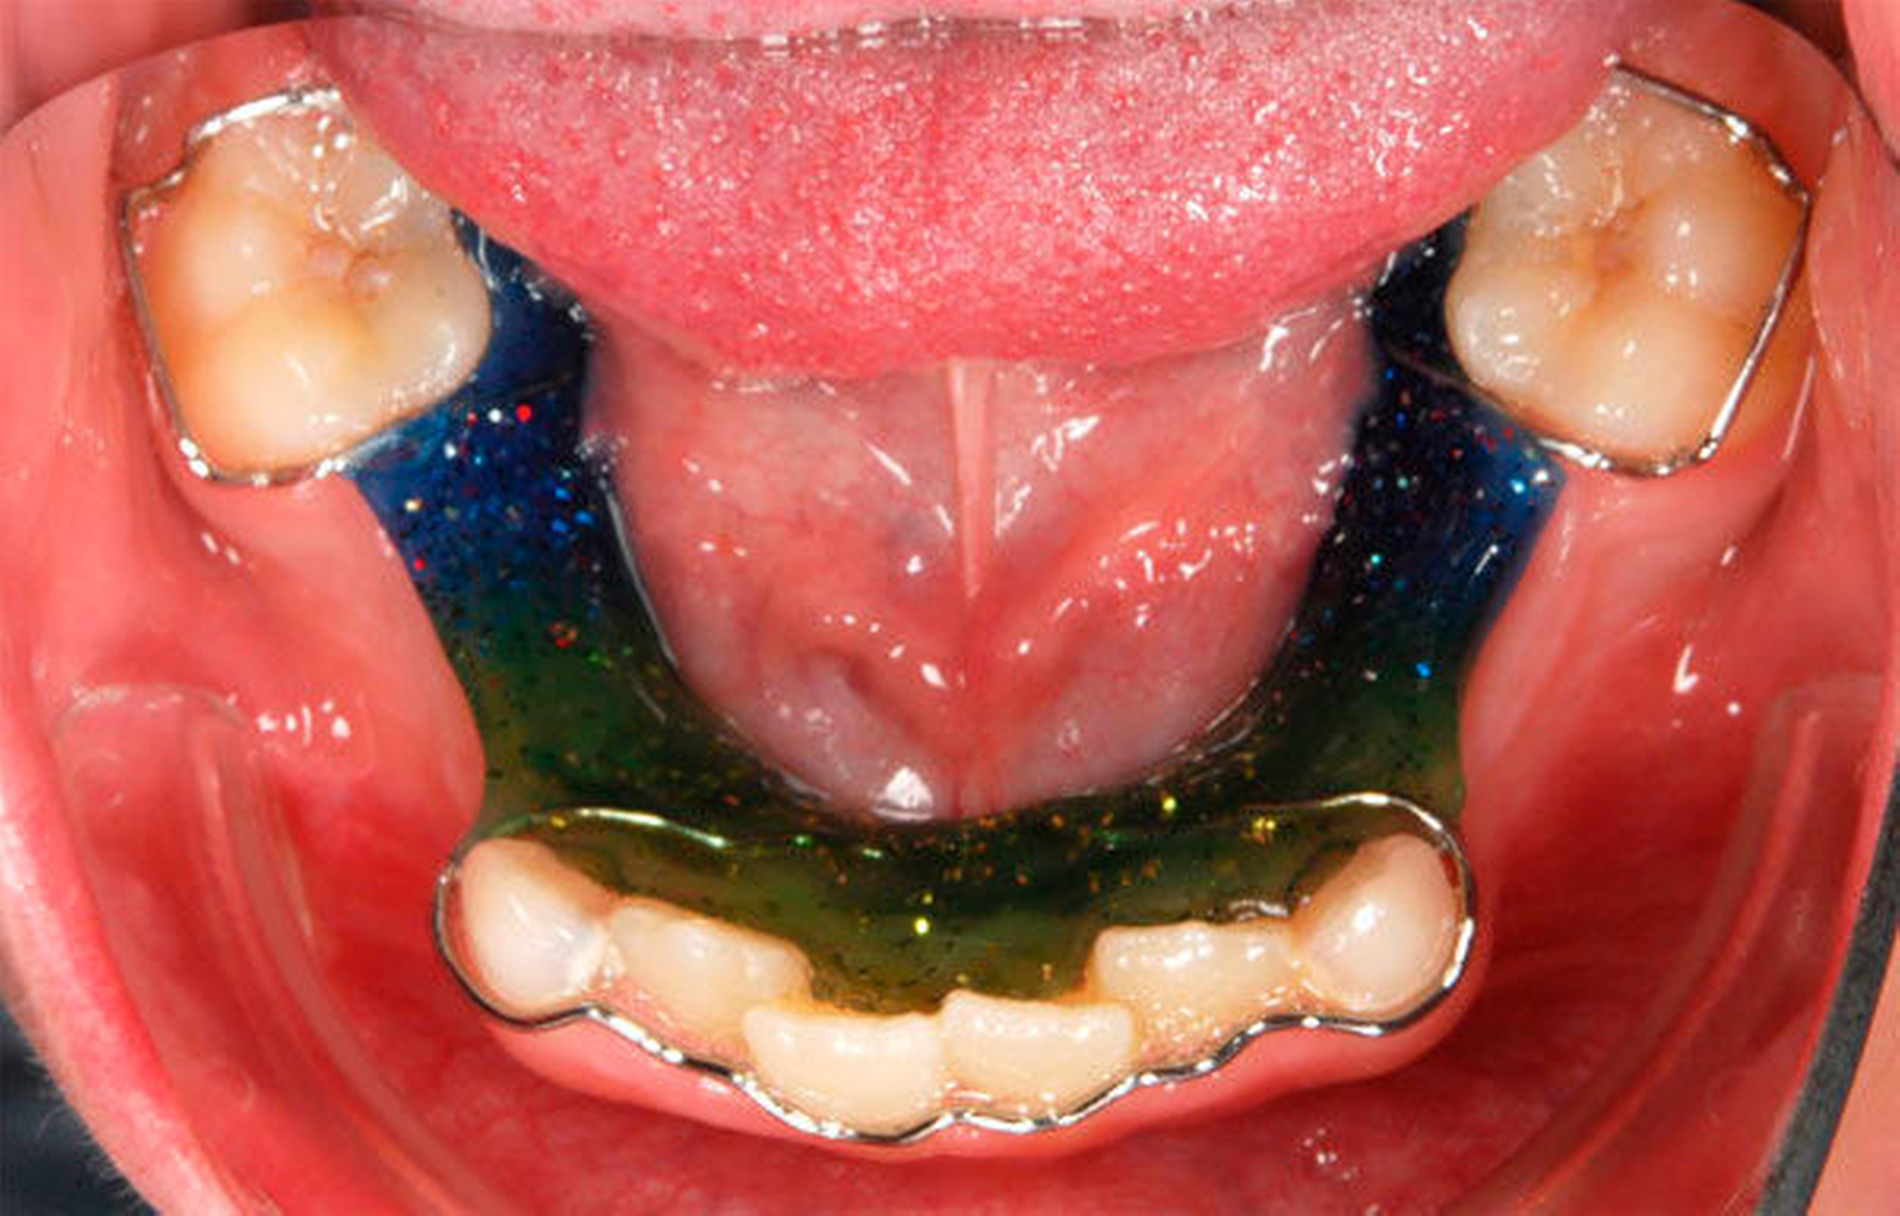

In dieser Phase der Entwicklung sollte ein besonderes Augenmerk auf die Platzverhältnisse in den Stützzonen gelegt werden, die wie beschrieben vom Milcheckzahn und den beiden Milchmolaren eines Quadranten gebildet werden. Diese Zähne sichern die Distanz zwischen den bereits durchgebrochenen permanenten seitlichen Inzisiven und dem Sechsjahrmolaren und somit den Raum für die später durchbrechenden permanenten Eckzähne und Prämolaren. Nach einem frühzeitigen Milchzahnverlust in der Stützzone kann es zu einer Elongation der antagonistischen Zähne kommen. Zudem besteht die Gefahr der Mesialwanderung des Sechsjahrmolaren. Durch diese Verringerung der Zahnbogenlänge kann ein Platzmangel für die später durchbrechenden Prämolaren beziehungsweise für den Eckzahn resultieren [Northway, 2000]. Daher wird bei frühzeitigem Milchzahnverlust, insbesondere bei Verlust der zweiten Milchmolaren oder der Milcheckzähne, das Eingliedern eines Lückenhalters empfohlen [DGZMK, 2004] (Abbildung 8).